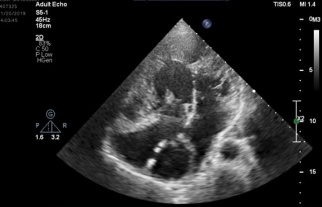

A 30 years old Male with history of complex congenital disease as  Abdominal and atrial situs solitus, , Levocardia , L-looped ventricles, Dominant left sided ventricle with RV morphology with moderate to severe systolic dysfunction(GEF:35%), also Both AV-valves empty to RV(DIRV),Moderate to severe left and right AV valve regurgitation, Both great arteries arise from dominant ventricle(DORV),Aorta was anterior and right sided to PA(D-malposition of great arteries),PA closed surgically with no ante grade flow,  confluent PA branches(RPA=1.4mm,LPA=1.4mm),Left sided aortic arch, Patent Glenn shunt with normal respiratory variation and low velocity laminar flow,Patent conduit between IVC and RPA with slow flow ,4mm fenestration with MPG:4 mmHg, Moderate size secondum type ASD( Fontan surgery, intracardiac tunnel with fenestration).(fig1,2,3)

Fig. 1: Echocardiography in standard apical 4 chamber showed  Both AV-valves empty to RV

Figure 1